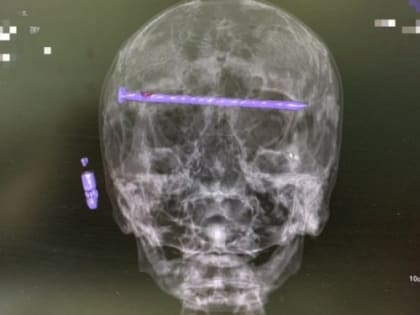

Сложнейшая операция в Нижнем Тагиле спасла жизнь 78-летнему пациенту

Врачи извлекли 15-сантиметровый гвоздь из головы пациента.